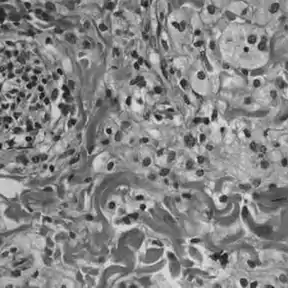

Histologically, ECD differs from Langerhans cell histiocytosis (LCH) in a number of ways. Unlike LCH, ECD does not stain positive for S-100 proteins or Group 1 CD1a glycoproteins, and electron microscopy of cell cytoplasm does not disclose Birbeck granules.[6] Tissue samples show xanthomatous or xanthogranulomatous infiltration by lipid-laden or foamy histiocytes, and are usually surrounded by fibrosis. Bone biopsy is said to offer the greatest likelihood of reaching a diagnosis. In some, there is histiocyte proliferation, and on staining, the section is CD68+ and CD1a-.